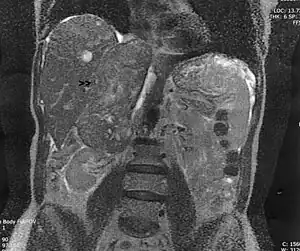

Leiomyosarcoma of the adrenal vein. Coronal view of abdominal MRI. Tumor (arrow) extends from the superior pole of the right kidney to the right atrium. | |